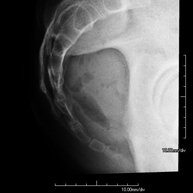

- RX ATM (Articulación Temporo-Mandibular)

Técnica mediante la cual, utilizando rayos X, se obtienen imágenes de la articulación temporo-mandibular para su estudio. Indicaciones: traumatismo, dolor al masticar, ruido al masticar, limitación en la apertura bucal.